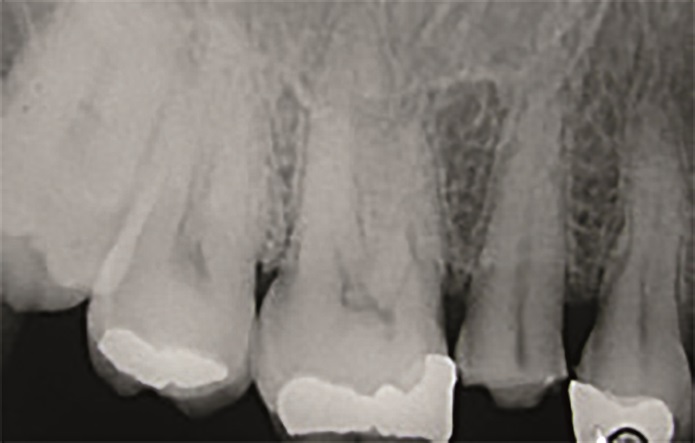

47‑letnia pacjentka zgłosiła się z powodu objawów zapalenia miazgi zęba 15. W badaniu wewnątrzustnym stwierdzono obecność starego wypełnienia amalgamatowego oraz złamanie guzka policzkowego zęba 15 (ryc. 1 i 2). W związku z tym na pierwszej wizycie przeprowadzono leczenie endodontyczne zęba 15 w znieczuleniu miejscowym (ryc. 3).